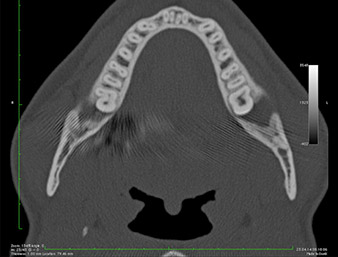

En la imagen en 3D (tomografía volumétrica digital) se constató que el resto radicular se encontraba muy desplazado en sentido distocaudal en la transición situada entre la porción horizontal y la ascendente del maxilar inferior (figura 2).

TVD transversal

Imagen 2: Representación de una TVD transversal del resto radicular en el espacio retromolar.